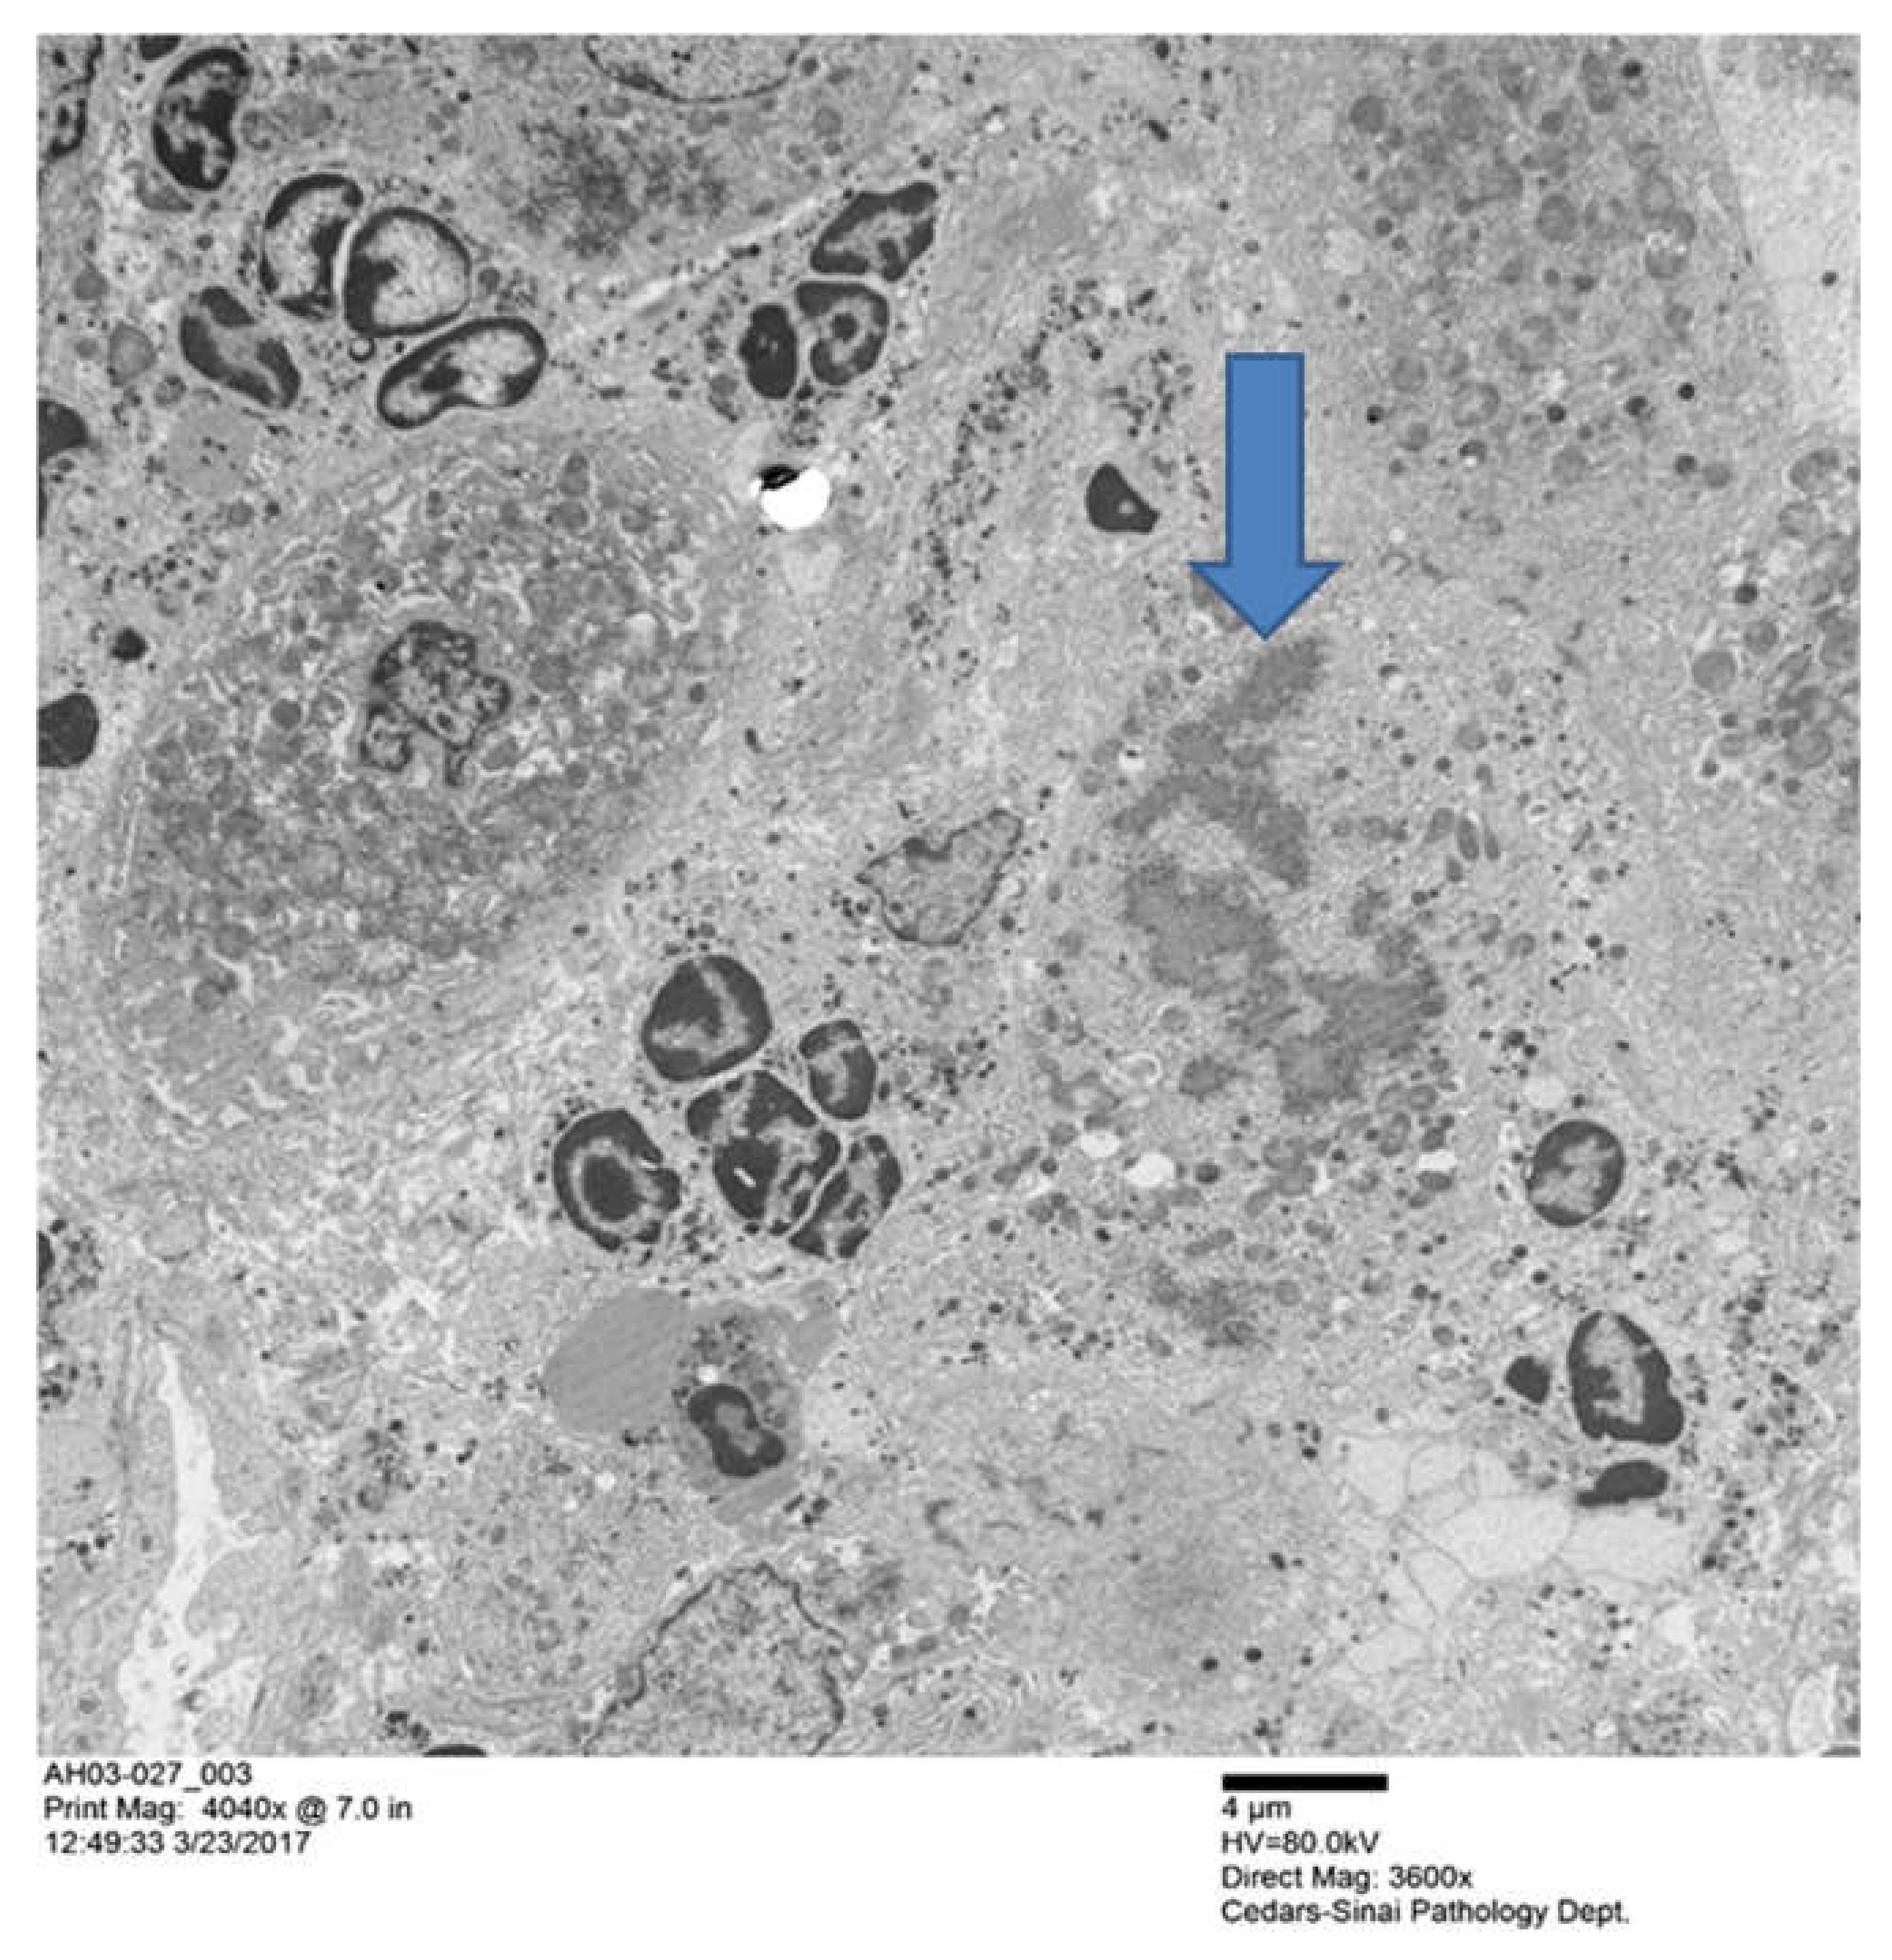

- Afifiyan, N.; Tillman, B.; French, B.A.; Sweeny, O.; Masouminia, M.; Samadzadeh, S.; French, S.W. The role of Tec Kinase signalling pathways in the development of Mallory-Denk bodies in balloon cells in alcoholic hepatitis. Exp. Mol. Pathol. 2017, 103, 191–199. [Google Scholar] [CrossRef]

| 03-027 | 1+ | 0 | 4+ | 4+ | PMN satellitosis | 4+ | 4+ |